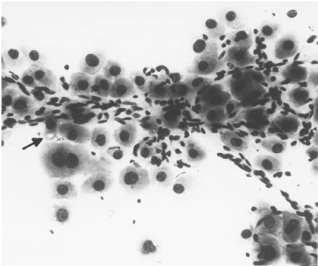

Fine needle aspiration cytology was performed under ultrasound guidance. Cytological examination from the gall-bladder mass and the liver mass, were of similar morphology. The highly cellular smears were composed of tumor cells resembling normal liver but were at least 3-4 times larger. The cells were arranged in trabeculae, loosely cohesive groups and lying singly. Parallel rows of spindle shaped fibrocytes were seen intermingled with the neoplastic cells. The cells had a large nucleus with prominent nucleoli. Cytoplasmic bile pigments were seen in many cells. Some of the nuclei showed intra nuclear cytoplasmic inclusion. Few atypical mitotic figures were also seen (Figure 3). A probable diagnosis of FL-HCC was given.

Figure 3. FNAC of the liver mass showing parallel rows of fibrocytes intermingled with tumor cells. Well defined pale body seen (arrow) in the cytoplasm of some cells.  (X 200)